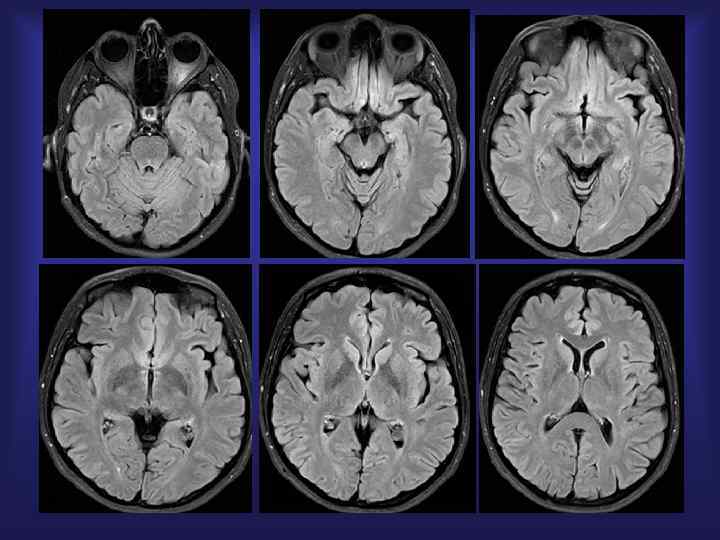

Лимфома (варианты локализации) Т 2 FLAIR T 1 +Gd

Комплексная МРТ диагностика первичной B-клеточной лимфомы головного мозга T 2 T 1 DWI b=1000 T 1+GD ADC MAP b=1000 Гипоперфузия СКТ-ПВИ